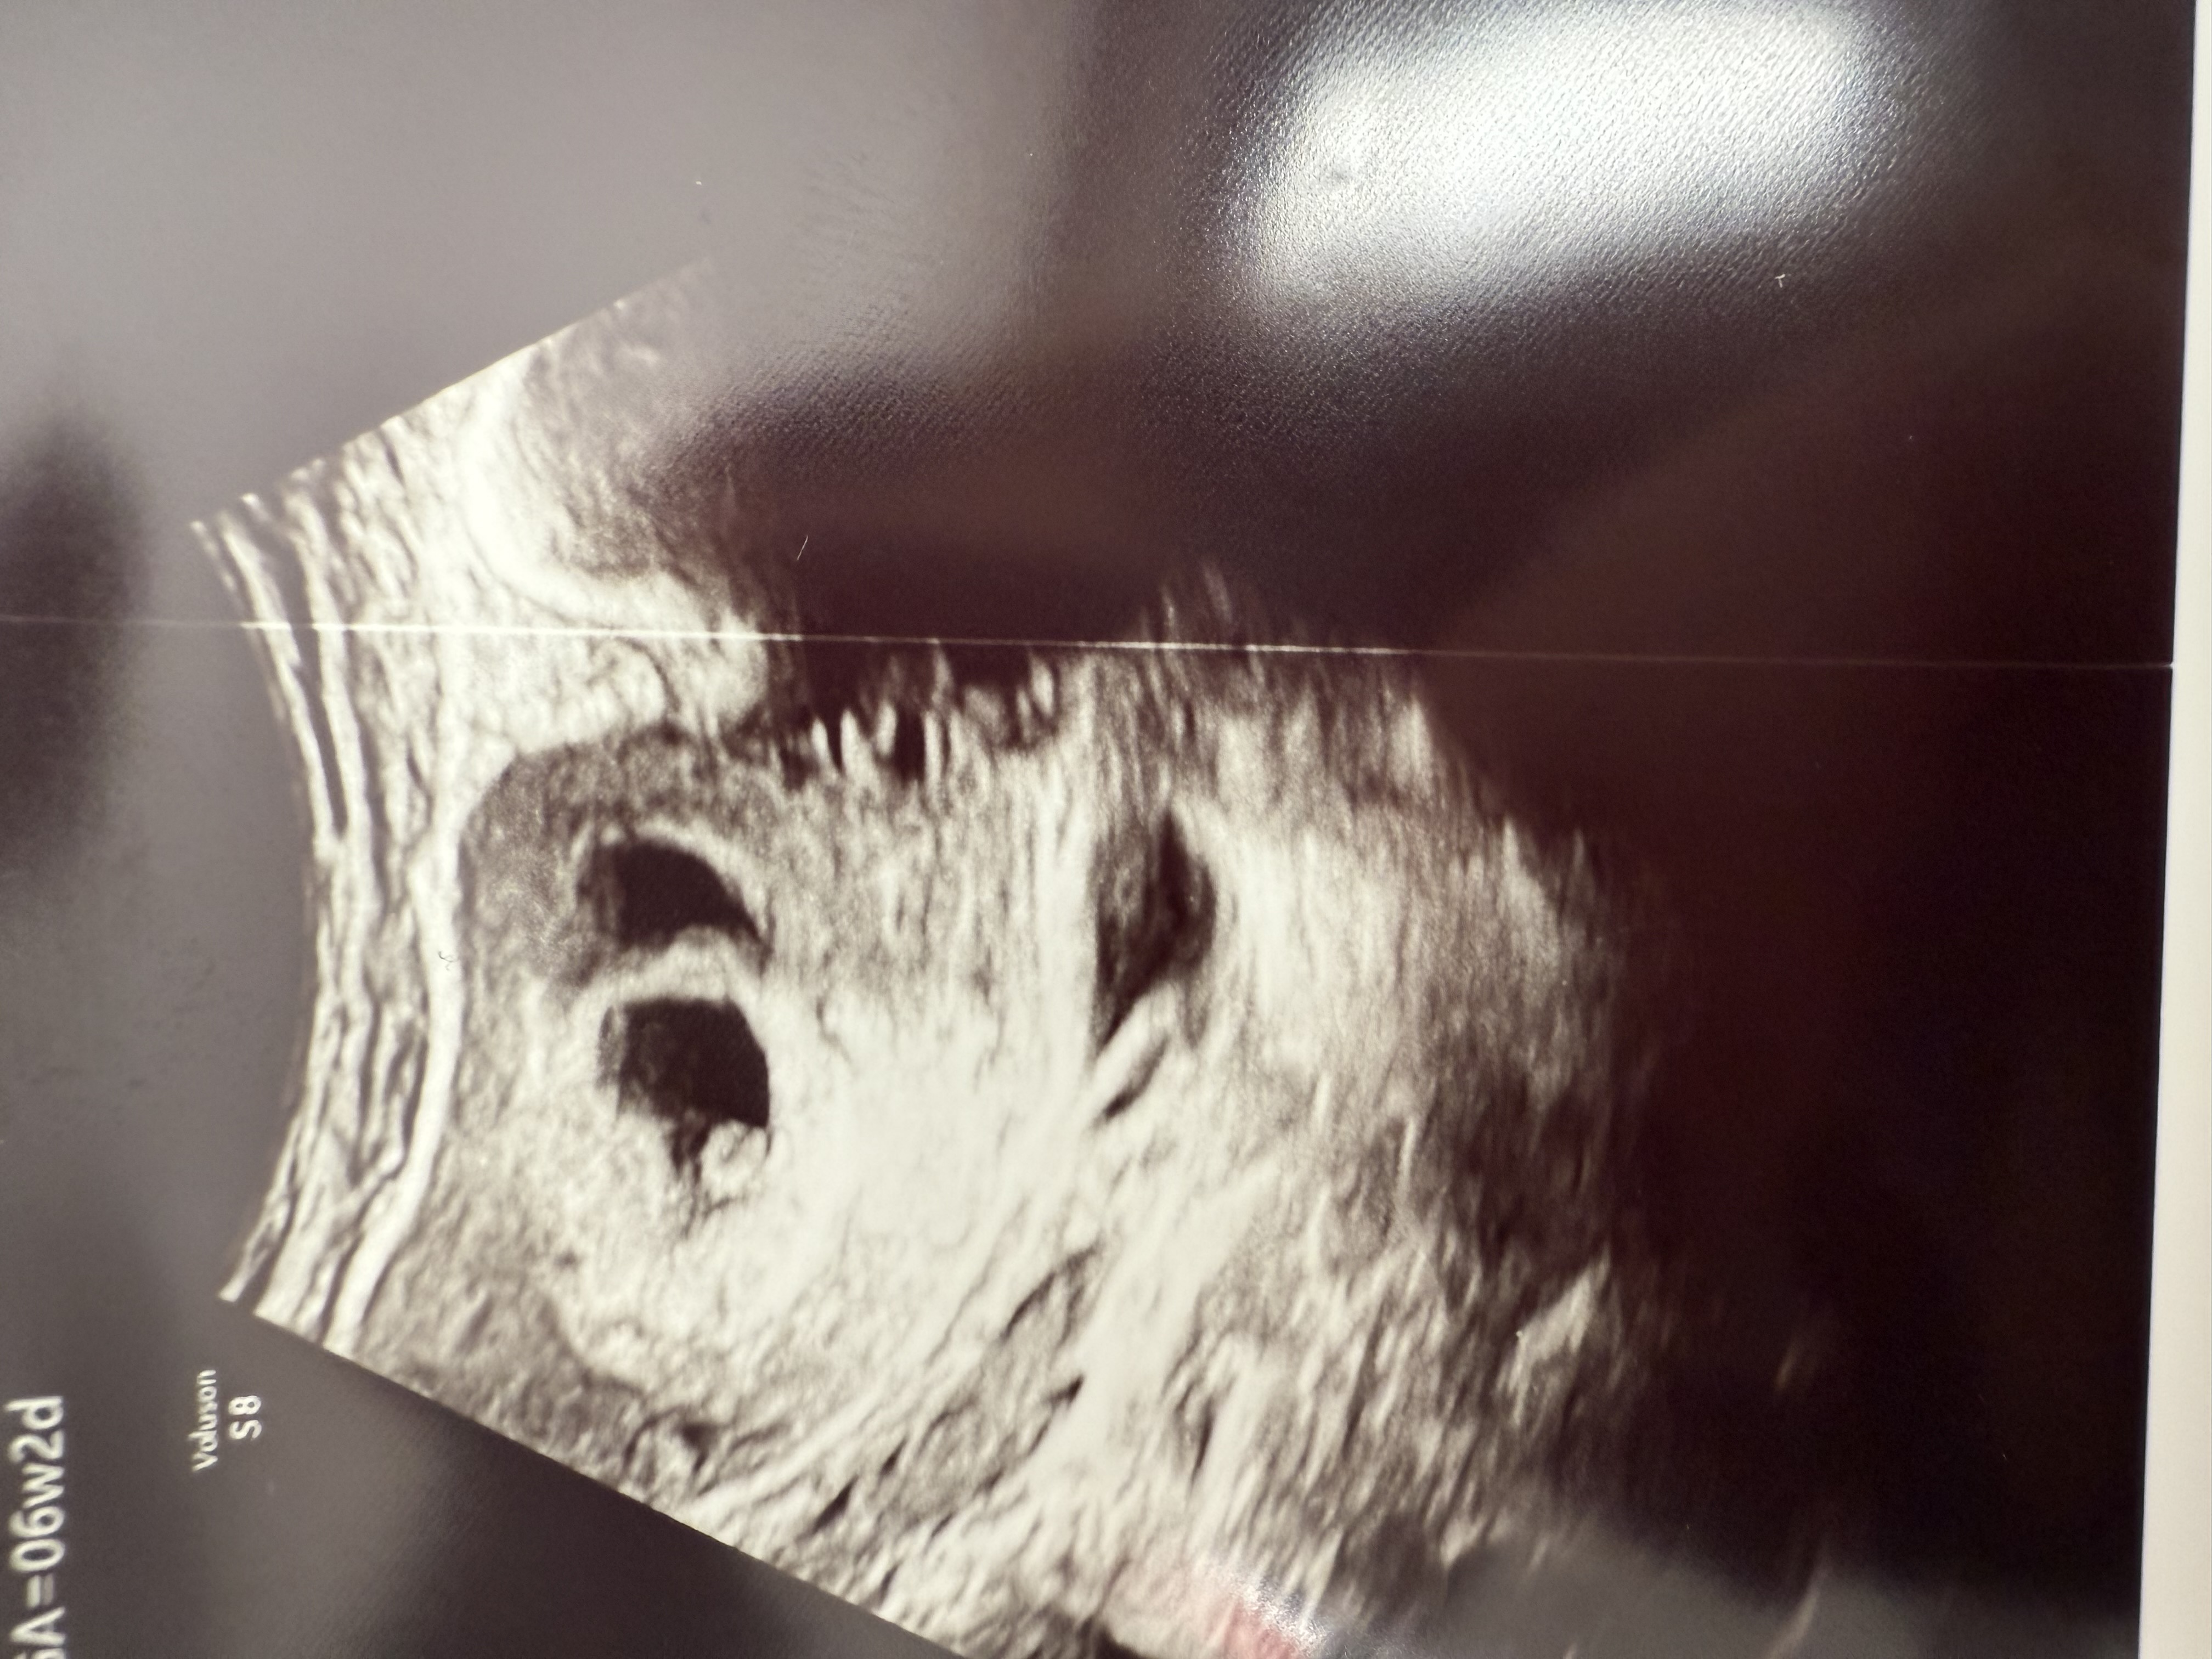

6 недель, второе плодное яйцо пустое

Была на первом узи сегодня, первый плод развивается согласно сроку, сердечко услышали, хорошо прикрепился, второе плодное яйцо очень рядом, но не обнаружили там эмбрион, сказали скорее всего уйдет, через неделю снова на узи, тогда будет точно ясно.

upd: сегодня была на повторном узи спустя неделю, второе плодное яйцо почти полностью ушло, там так никто и не появился, с первым все в порядке, растем😊